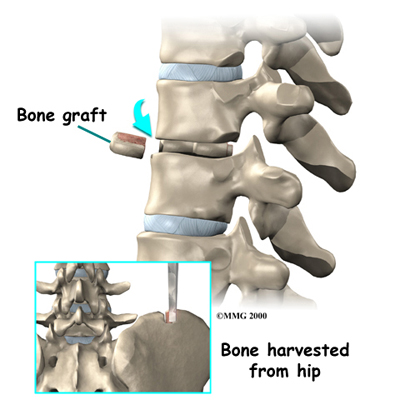

After removing part or all of the disc, the spine may be loose and unstable. Fusion surgery may be needed immediately afterward. The medical term for fusion is arthrodesis. This procedure locks the vertebrae in place and stops movement between the vertebrae. This steadies the bones and can ease pain. Fusion surgery is not usually needed if only a small amount of bone and disc material was removed during surgery to fix a herniated thoracic disc.

In this procedure, the surgeon lays small grafts of bone over or between the loose spinal bones. Surgeons may use a combination of screws, cables, and rods to prevent the vertebrae from moving and allow the graft to heal.